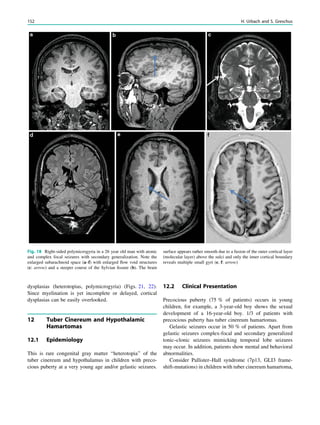

Fig. 1 Digital photogram of the brain surface before placement of a

subdural 8 9 8 grid. A second photogram was taken after grid

placement and digitally replaced by a schematic drawing detailing the

results of electrical stimulations and ictal/ intraictal EEG activity. Blue

grid contacts represent the eloquent zone, which is the motor cortex in

this case. The black area represents the epileptogenic lesion, defined

as the radiographic lesion that causes the seizures. The yellow area is

the seizure onset zone, defined as the area from which the clinical

seizures are generated. The seizure onset zone is often, but not

necessarily, congruent with the epileptogenic zone, defined as the

cortex area indispensable for the generation of seizures

Fig. 2 Epileptogenic lesion and symptomatogenic zone. A 40-year-

old woman suffered from complex focal seizures with a fearful face

and body rocking. The symptoms thus pointed to the mesial frontal

lobe as the origin. MRI shows right-sided hippocampal sclerosis

(a, arrow). Simultaneous video and EEG recordings from interhemi-

spheric (c) and convexity strip and intrahippocampal depth (b) elec-

trodes show seizures starting in the right hippocampus (d, arrow).

Clinical symptoms start around 1 s afterwards (d, asterisk)

22 H. Urbach

seizure onset zone which it is intended to be removed, and

this is defined as the brain area in which ictal EEG activity

starts. The epileptogenic lesion usually shows at least some

overlap with the seizure onset zone and is therefore a good

indicator for its localization (Fig. 1).

Other frequently used terms are irritative area, defined as

the brain area with interictal EEG activity, eloquent cortex,

defined as the cortex area with important functions such as

language, motor, and visual field functions, and symptoma-

togenic area, defined as the brain area in which epilep-

togenic activity leads to clinical symptoms. If epileptogenic

activity spreads rapidly, the epileptogenic lesion and the

symptomatogenic area can be far from each other (Fig. 2).